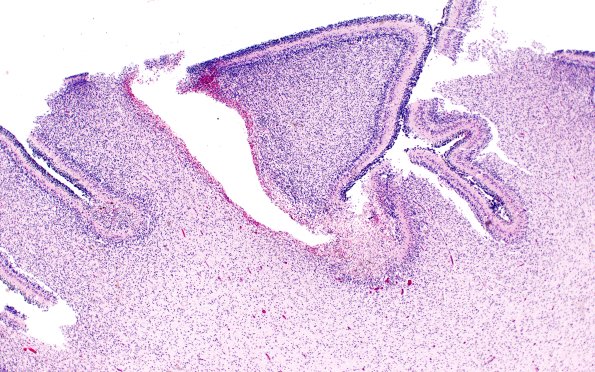

Washington University Experience | VASCULAR | Hemorrhage - Neonatal | 27B1 Hypoxia-Ischemia, premature (Case 27) H&E 5A

27B1-5- These are multiple foci of subpial hemorrhage which produce, possibly by vasospasm, areas of ischemia and neuron loss, often at the depts of the folia (a microwatershed?). (H&E)